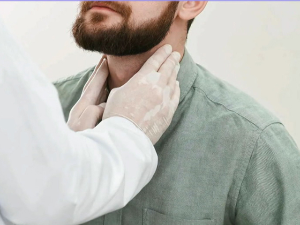

Подмукла, али излечива болест ако се утврди на време – Хочкинов лимфом

У Србији се сваке године дијагностикује око 250 нових случајева Хочкиновог лимфома – малигног обољења које најчешће погађа младе између 15. и 40. годинe...